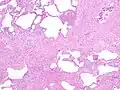

Histology

The histologic hallmarks of UIP, as seen in lung tissue under a microscope by a pathologist, are interstitial fibrosis in a "patchwork pattern", honeycomb change and fibroblast foci (see images below).[6] [7]

Appearance of usual interstitial pneumonia (UIP) in a surgical lung biopsy at low magnification. The tissue is stained with hematoxylin (purple dye) and eosin (pink dye) to make it visible. The pink areas in this picture represent lung fibrosis (collagen stains pink). Note the "patchwork" (quilt-like) pattern of the fibrosis.

Appearance of honeycomb change in a surgical lung biopsy at low magnification. The dilated spaces seen here are filled with mucin. Hematoxylin-eosin stain, low magnification.